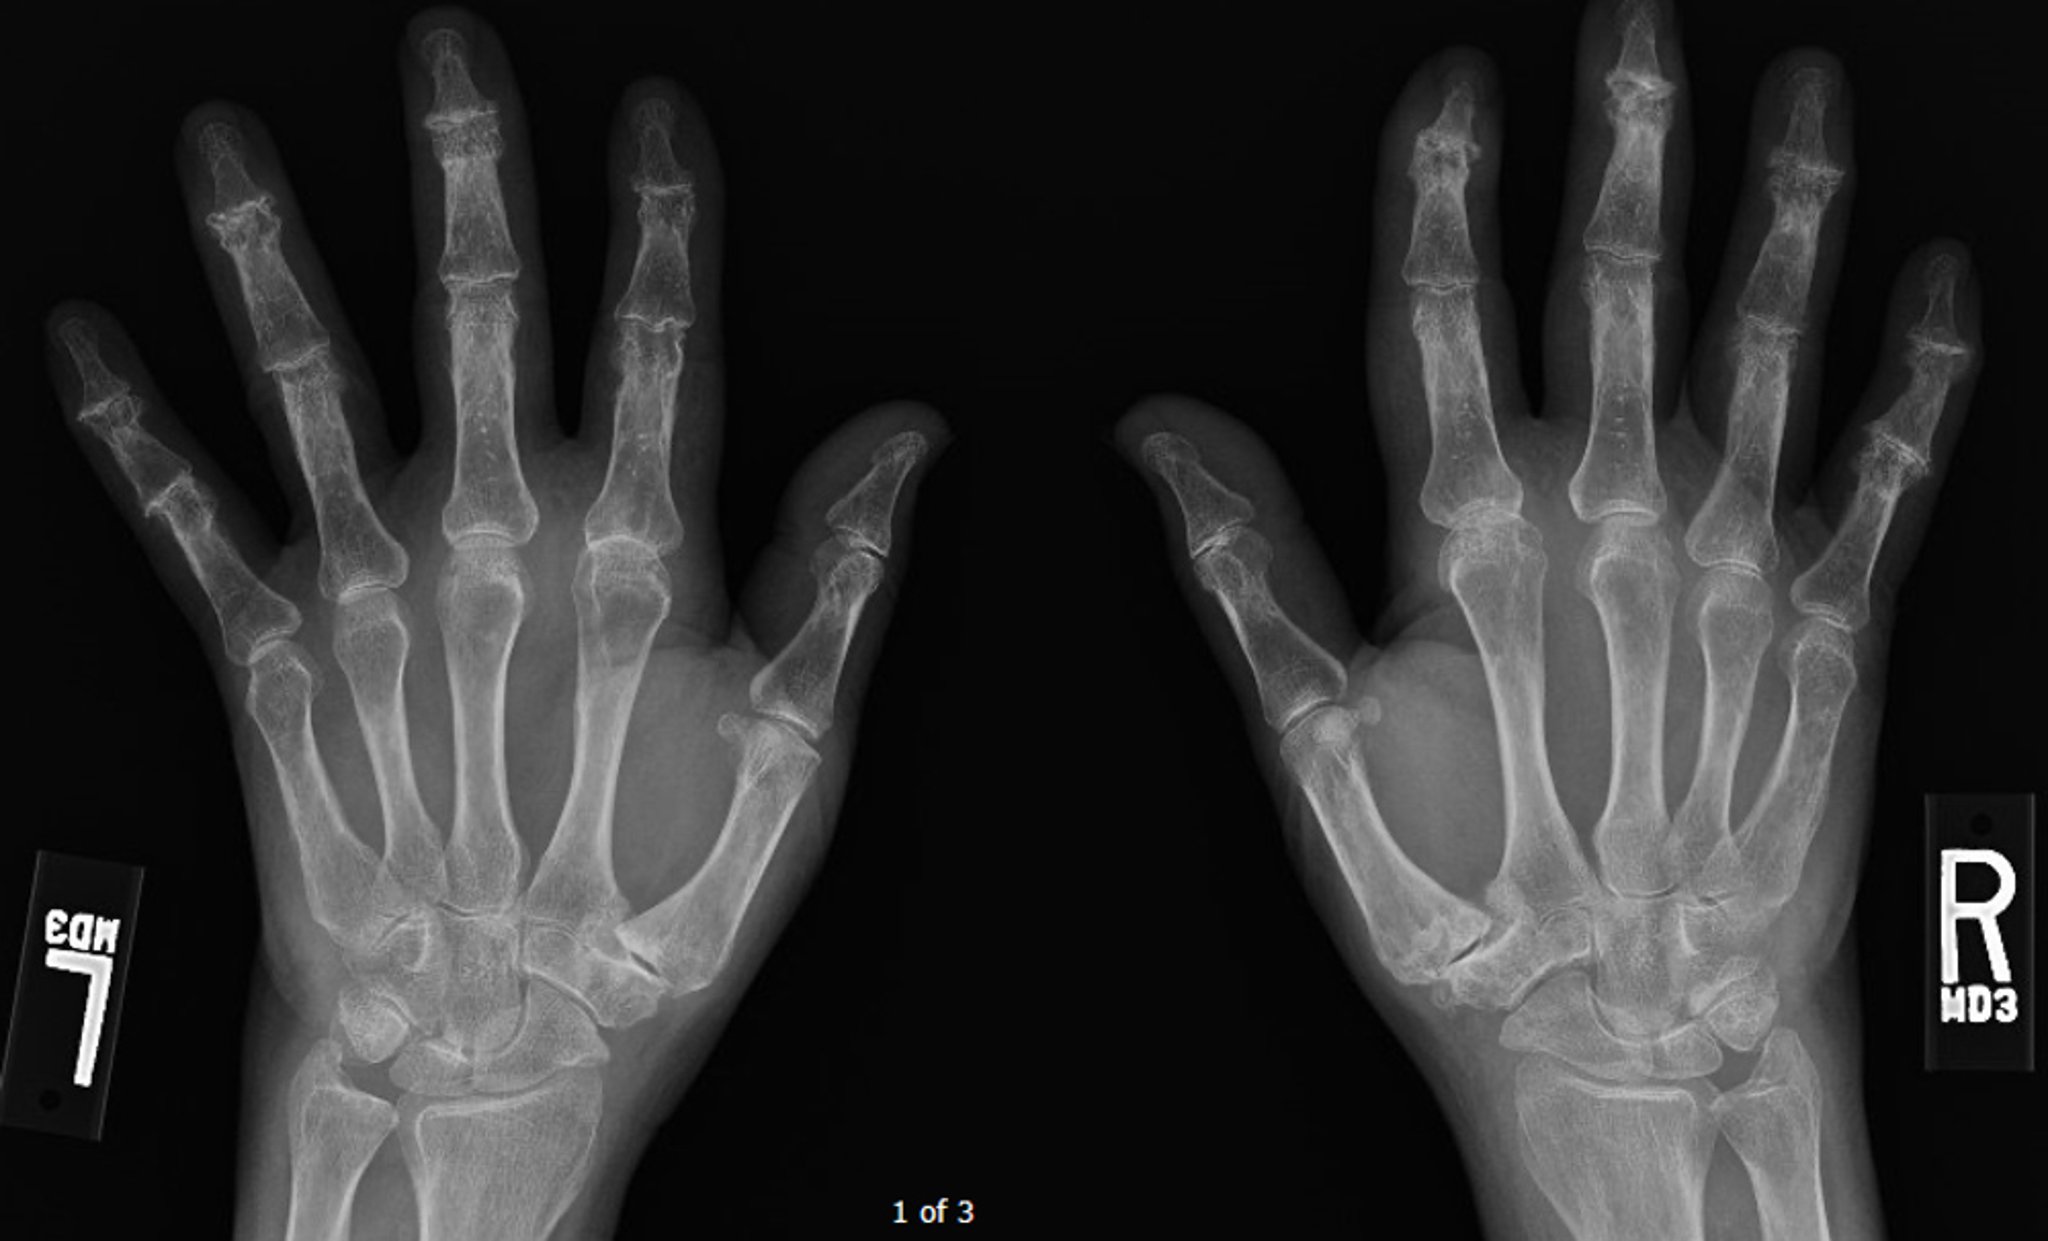

Thoái hóa khớp ăn mòn

Hình ảnh X-quang này cho thấy thoái hóa khớp lan tỏa giai đoạn tiến triển, nổi bật nhất là ở các khớp gian đốt xa, có thể nhìn thấy một số vết trợt ở trung tâm ở các khớp này.

Hình ảnh do bác sĩ Kinanah Yaseen cung cấp.